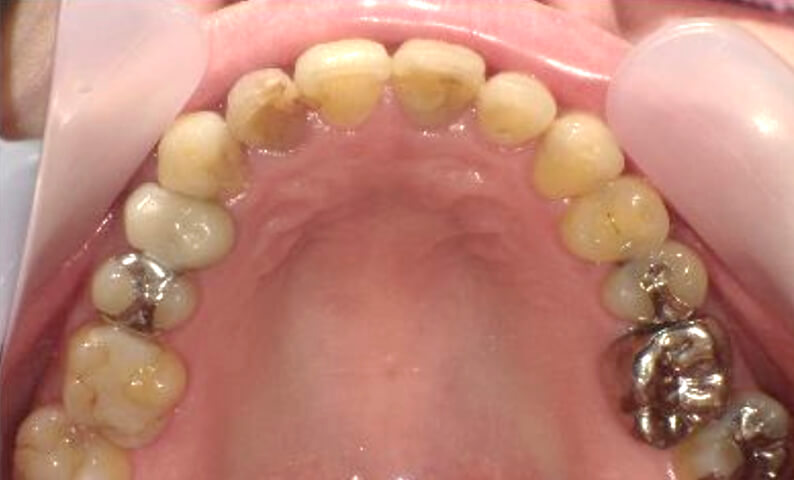

症例_003 下顎だけの部分矯正

治療期間:10ヶ月金額:24万円+税女性前歯のガタガタ下の前歯だけ上顎は補綴治療中

| Before | After |